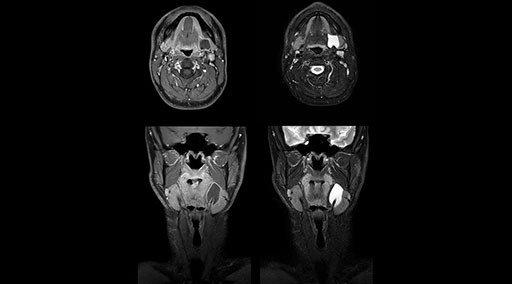

“Without using an endorectal coil we do our prostate MR at 0.5 mm resolution, following the European society of urology protocol [1]. For certain joints we use a virtual arthroscopy protocol with 1 mm pixel size and 2 mm slice thickness. Ingenia really excels in our neurography, brachial plexus and prostate scans. Our neurologists insist on using our 3.0T for those,” Dr. Kaakaji adds.

“Our DMG Lisle location includes a cancer center, so soft tissue neck scans, brachial plexus scans, and prostate scans are common. For these exams, mDIXON TSE provides excellent images with and without fat suppression all while helping us reduce repeats and work more efficiently,” Mr. Duffy says.

fat suppression. Neck exams and rheumatology patients are two examples where mDIXON TSE is especially useful,” Dr. Kaakaji says. “For us it’s also an efficiency boost in exams where we need pre and post T1-weighted images with great fat suppression.”